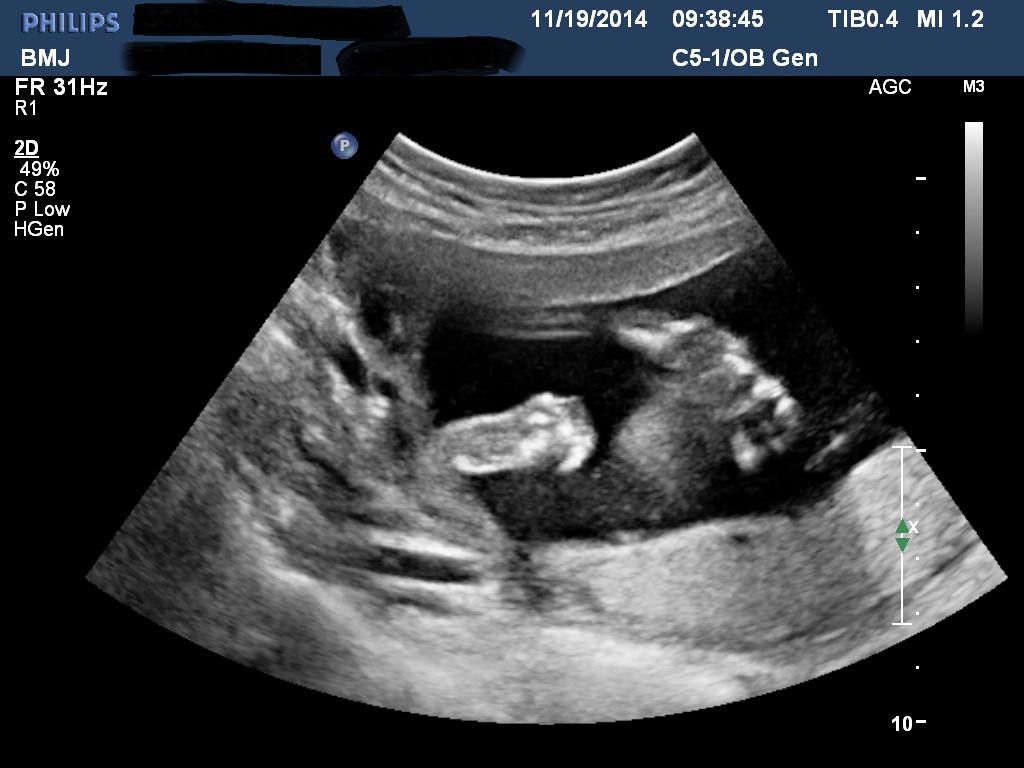

Bumps and U/S pics go here!!!